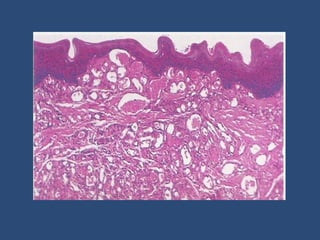

Histological appearances

 The overall low-power

architecture in all cases,

regardless of the organ

involved, is that of a

multilobulated tumor

 In early lesions, the lobules

are highly cellular and

composed of mitotically

active, plump endothelial

cells forming tiny, rounded,

often uncanalized vascular

spaces

 As lesions mature, the vessels become

canalized and more easily recognized, then

often showing congested lumina and flat

endothelial cells.

 Older lesions become progressively fibrotic

with almost complete regression or absence

of the vascular elements.